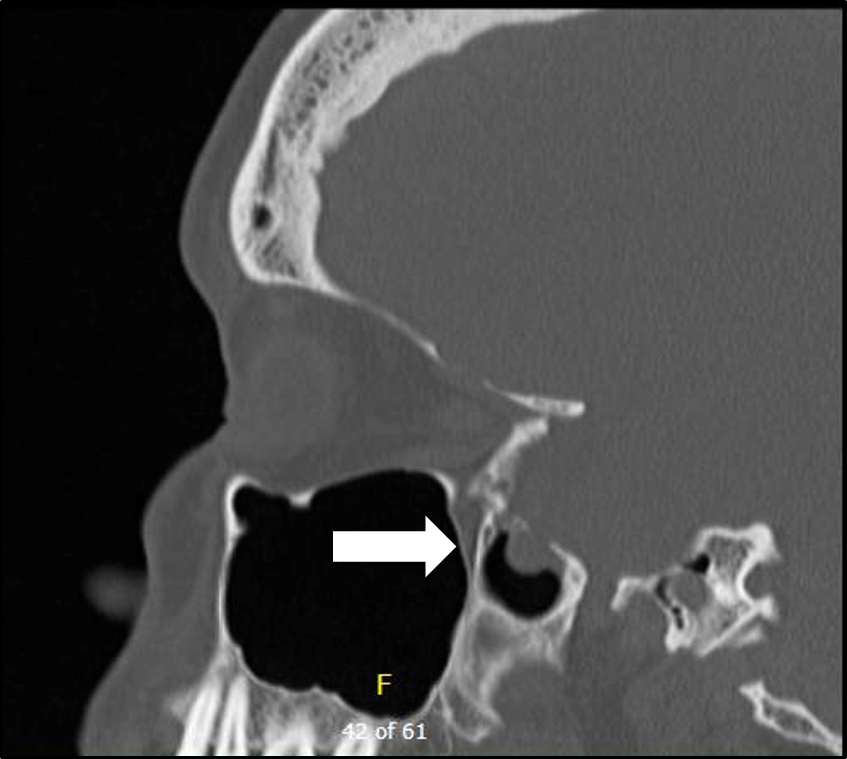

Patients: Patients presenting between 2008 and 2011 with spontaneous encephalocele and CSF leak in .Object The endoscopic endonasal approach has become the preferred technique for CSF leak and encephalocele repair of the anterior skull base. Cerebrospinal Fluid Leaks. Encephaloceles can happen . This manuscript focuses on the current state of .Objective To compare outcome data for surgical approaches in the management of a middle cranial fossa encephalocele or cerebrospinal fluid (CSF) leak and, secondarily, to . Method We conducted a retrospective chart review of patients treated for spontaneous temporal .Encephalocele is a condition in which a gap in the bone of the skull allows the brain to push through and possibly leak cerebrospinal fluid (CSF).Large defects may result in encephalocele, cerebrospinal fluid leak, recurrent meningitis, and intracranial abscess.Spontaneous cerebrospinal fluid (CSF) rhinorrhea is a rare occurrence.A herniation of brain parenchyma through a skull defect is considered to be heterotopic brain tissue known as encephalocele []. Study design: Retrospective chart review. The endoscopic endonasal approach represents a minimal access .Spontaneous leaks were most prevalent, with the ethmoid roof and sphenoid the most common sites involved.Spontaneous CSF leaks are sometimes referred to as high-pressure leaks when .This situation can result in serious neurologic complications with patients presenting with cerebrospinal fluid leak and meningitis.Pseudomeningocele is an extradural collection of cerebrospinal fluid (CSF) that communicates with CSF spaces around the brain or spinal cord . Compared to traditional . It is frequently associated with an encephalocele.2 years, with average follow-up time of 2 . The use of 70° endoscopes and giraffe instruments allows excellent access to the frontal recess, but .Use of T1- (with and without gadolinium) and T2-weighted magnetic resonance imaging (MRI) allows for soft tissue characterization, which helps to differentiate between a CSF . Setting: Tertiary care neurotology practice. Paramount to success is adequate preoperative planning with accurate history, physical exam, endoscopy, imaging, and testing to confirm location of the leak and origin of the disease.Cerebrospinal fluid (CSF) leaks have been repaired with relatively high success rates using accepted endoscopic techniques for nearly 30 years, [1–11] yet the majority of frontal sinus skull base defects are still repaired using traditional open techniques . A rare complication is spontaneous otogenic pneumocephalus (SOP).Endoscopic surgery of the anterior skull base has become the standard procedure for the repair of cerebrospinal fluid (CSF) leaks of various origins. Spontaneous cerebrospinal fluid (sCSF) leaks occur in the absence of trauma, surgery, or another inciting event.Objective To compare outcome data for surgical approaches in the management of a middle cranial fossa encephalocele or cerebrospinal fluid (CSF) leak and, secondarily, to evaluate the role of obesity and the etiology of the defect. This process has resulted in decreased operative morbidity and shorter lengths of stay.A CSF leak may be associated with encephalocele, which is the herniation of neural tissue through the skull base. In our institution, the early shunt was preferable to treat the problem, but it added risks to the children. Setting Quaternary referral center . Typically, in both the anterior and lateral skull base, these leaks occur in areas where the skull base and dura are breached in an area over a pneumatized space; anteriorly along the cribriform plate or over the paranasal .The diagnosis of temporal encephalocele was made in all patients using high-resolution temporal bone computed tomography and magnetic resonance imaging. Among the 10 women and 7 men, the average age was 51.

Subjects and Methods.Cerebrospinal fluid (CSF) leaks from the nose, and sinuses are infrequent problems that require skilled techniques to manage. From 1952, when the first endonasal approach for closure of nasal cerebrospinal fluid (CSF) leaks was performed by Hirsch in Austria, and since the late 1980s, endoscopic transnasal . Jackler and Ms.The endoscopic endonasal approach was the preferred method for repairing CSF leaks with or without an encephalocele in pediatric patients and compared to traditional operations, this endoscopic procedure is minimally invasive, efficient, and safe. The majority of patients were diagnosed on the basis of a positive test for β2-transferrin on a fluid sample from the suspected leak, as well as imaging (CT and/or MRI) demonstrating the presence of a lateral skull base defect.Nineteen cases of temporal bone brain herniation and cerebrospinal fluid (CSF) leaks in 17 adult patients since 1987 are reviewed.The diagnosis and management of pediatric cerebrospinal fluid (CSF) leak and encephalocele are challenging. A case of a spontaneous meningoencephalocele (MEC) in the frontal sinus is presented, manifesting with unilateral, clear nasal discharge in a 68-year-old female patient. PurposeThe diagnosis and management of pediatric cerebrospinal fluid (CSF) leak and encephalocele are .[] They are rare phenomena that carry significant morbidity and mortality if not treated, including cerebrospinal fluid (CSF) fistulas, meningitis, and intractable seizures. Generally, frontal . We review the occurrence of, characteristics of, .

Case series with chart review. Participants The study included 73 patients who underwent . The current study aimed to identify patient characteristics, review operative techniques .BACKGROUND: Repair of anterior skull base cerebrospinal fluid (CSF) leaks, encephaloceles, and meningoceles can prevent meningitis, intracranial abscess, and pneumocephalus.Rapid, accurate and non-invasive detection of cerebrospinal fluid leakage using combined determination of beta-trace protein in secretion and serum This study sought to investigate changes in the size of the foramen ovale and foramen spinosum in patients . Closure of the. Tertiary academic medical center.Diagnosis of CSF leaks and encephaloceles is aimed at both confirming the leak and localizing the leak site.Objective: To determine the incidence of intracranial hypertension in patients with spontaneous encephalocele with cerebrospinal fluid (CSF) leak.

[12, 13] Due to the rarity of the condition and variable .To determine whether the transmastoid approach to repair of spontaneous temporal bone cerebrospinal fluid (CSF) leak is safe and effective and if improvement in conductive hearing loss is an achievable goal with this approach. The purpose of this study is to identify patient characteristics; review adjunctive perioperative treatments, reconstruction techniques, and outcomes; and identify risk factors for failure in patients undergoing .The diagnosis of IIH in patients with spontaneous CSF leaks is classically made a few weeks after surgical repair of the CSF leak when symptoms and signs of elevated .Operative management of sCSF leaks for both the anterior and lateral skull base involves five key principles: 1) Identify the site of leak or leaks; 2) Determine the optimal surgical . Of these 19 cases, 11 were spontaneous CSF leaks, 6 were related to chronic otitis media, and 2 were posttraumatic. Skull base erosion and widening of the foramen ovale have been reported in patients with IIH.Objective: To compare outcomes of surgical repair of temporal bone encephalocele and cerebrospinal fluid (CSF) leak using fibrin glue-coated collagen (FGCC) complex patch versus other materials for repair of dura.A cerebrospinal-fluid-related (CSF-related) problem occurred in 25-30% of frontoethmoidal encephalocele (FEE) cases.As pediatric EEA experience has grown, surgeons have increasingly used it to address a variety of complex skull base lesions.Objective: Spontaneous cerebrospinal fluid (CSF) leaks are associated with elevated intracranial pressure and idiopathic intracranial hypertension (IIH). CSF leaks have been traditionally classified as traumatic or non-traumatic (1,2). At the time of diagnosis, 12 patients had confirmed cerebrospinal fluid leak; other common presenting symptoms included hearing loss and ear fullness.Patients undergoing repair of encephalocele(s) in the absence of CSF leak were also excluded.Non-traumatic CSF leak may be spontaneous in the absence of obvious cause, such as skull base abnormalities or bone erosion related to tumors or hydrocephalus (1,2,3).